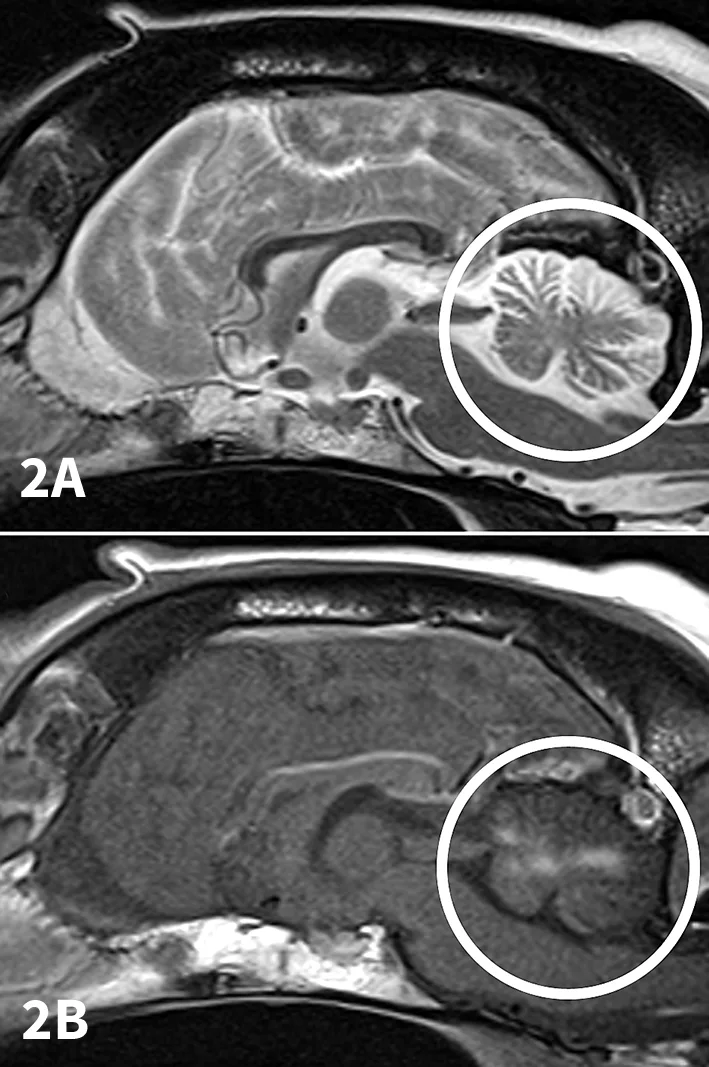

Figure 3

Photomicrograph showing N caninum bradyzoite-containing cyst (arrow) in brain tissue from a different clinical case (20× objective).